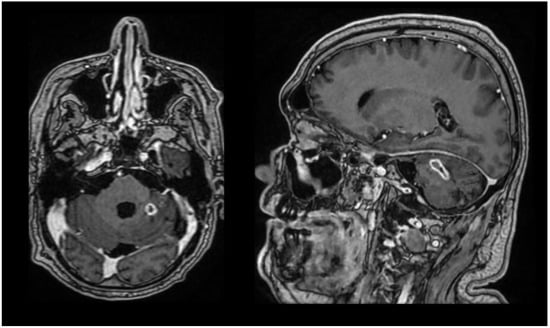

One week before discharge, the brain MRI (Figure 2) showed a postoperative meningocele unchanged compared to the previous examination, occipital craniectomy, and a lesion in the left cerebellar hemisphere, imaging-compatible with an abscess, relatively stable in size compared to the prior study, with chronic inflammatory changes in the bilateral maxillary sinuses.

Figure 2.

Brain MRI one week before discharge in axial and sagittal section.